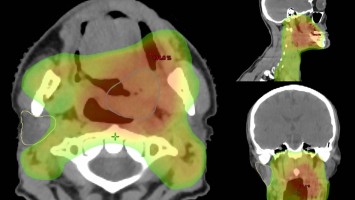

Neues in der Radiochemotherapie von Kopf-Hals-Tumoren

Kutane Arzneimittelreaktion/© Hötzenecker, W., Heimlich-Manöver/© Widmer, N; Heimes, D / all rights reserved Springer Medizin Verlag GmbH, Aufbau bei einer endoskopische Mittelohrchirurgie/© Mir-Salim P., Berlin, Wespen auf Stein/© merlion / Getty Images / iStock (Symbolbild), Schilddrüse einer Patientin wird untersucht/© Werner / stock.adobe.com (Symbolbild mit Fotmodellen), Volumetrie des Bulbus olfactorius/© Keweloh S.. et al. doi.org/10.1007/s00106-025-01650-z unter CC-BY 4.0, Augen und Nase einer Frau/© AlexanderFord / Getty Images / iStock (Symbolbild mit Fotomodell), Eine ältere Frau schaut in die Ferne/© RgStudio / Getty Images / iStock (Symbolbild mit Fotomodell), Transnasales Ösophagoskop/© F. Michel, Seeheim-Jugenheim, Ex vivo konfokales Laserscanmikroskopiebild eines Morbus Bowen/© Grunewald S et al. / all rights reserved Springer Medizin Verlag GmbH, Einweckglas mit Hering/© FoodieMedia / Getty Images / iStock (Symbolbild), Zwei Injektionspens mit Semaglutid/© Kassandra / Stock.adobe.com, Gewitter mit Blitzschlag/© solarseven / Getty images / iStock, Ulzerative Form des oralen Lichen planus/© Abdusalamov K. et al. doi.org/10.1007/s00105-025-05540-x unter CC-BY 4.0, Otitis externa/© Dr. P. Marazzi / Science Photo Library (Symbolbild), VMAT-Bestrahlungsplan einer definitiven Radiochemotherapie eines linksseitigen, lokal fortgeschrittenen Tonsillenkarzinoms/© Schnellhardt, S et al. / all rights reserved Springer Medizin Verlag GmbH, Frau hustet/© Suzi Media Production / Getty Images / iStock (Symbolbild mit Fotomodell), Tympanometrie bei einer Frau/© Viacheslav Yakobchuk (Symbolbild mit Fotomodell), Stimmlippeninjektion in der HNO-Praxis/© Markus Hess, Mann erhält eine Spritze im Gesicht/© Alvaro / Stock.adobe.com (Symbolbild mit Fotomodell), Ein Arzt sprüht ein antimikrobielles und entzündungshemmendes Spray in den entzündeten Hals eines Mädchens./© HENADZY / Stock.adobe.com (Symbolbild mit Fotomodell), Junger Mensch bekommt Spritze verabreicht/© mapo / Getty Images / iStock (Symbolbild mit Fotomodellen), Bestrahlungsplans einer Wirbelsäulenmetastase eines oligometastasierten Prostatakarzinoms/© Springer Medizin Verlag GmbH, Cholesterolgranulom im MRT/© Frederik F/ all rights reserved Springer Medizin Verlag GmbH, Schimmelbefall an der Wand/© Bigy / Stock.adobe.com (Symbolbild), Rasterelektronenmikroskopische Aufnahme von Nanopartikeln/© Hansen S. et al. doi.org/10.1007/s00106-025-01633-0 unter CC-BY 4.0, Medulläres Schilddrüsenkarzinom linker Schilddrüsenlappen in der Sonographie/© Lorenz K et al. / all rights reserved Springer Medizin Verlag GmbH, Sonnenhüte (Echinacea)/© Wieland Teixeira / Getty Images / iStock (Symbolbild mit Fotomodell), Körperstereotaxie einer Lebermetastase im Segment VIII am MR-LINAC/© Ehret, F. et al. / all rights reserved Springer Medizin Verlag GmbH, Eine ältere Frau riecht an einem Basilikumblatt/© Halfpoint / Stock.adobe.com (Symbolbild mit Fotomodell), Mann hustet/© kostyha / stock.adobe.com (Symbolbild mit Fotomodell), Titel/© J. Hornung, Erlangen, Senior hält sich vor Schmerzen an den Hals/© brizmaker / Getty Images / iStock (Symbolbild mit Fotomodell), Chor von älteren Menschen/© Highwaystarz-Photography / Getty (Symbolbild mit Fotomodellen), Eine junge Frau spült sich mir einer Nasenspülung die Nase/© puhhha / Getty Images / iStock (Symbolbild mit Fotomodell), Kleiner Junge mit Pille auf der Zunge/© redpepper82 / stock.adobe.com (Symbolbild mit Fotomodell), Frau mit Kopfschmerzen/© MaximFesenko / Getty Images / iStock (Symbolbild mit Fotomodell), Normaler Verlauf nach Hirntumor?/© Wolfgang Freund, Szintigraphie der Schilddrüse mit zwei Knoten/© AniphaeS / Getty Images / iStock, Patient mit Bauchschmerzen beim Arzt/© anon / Stock.adobe.com (Ausschnitt; Symbolbild mit Fotomodellen), Mann erleidet Schwindel/© Tunatura / Getty Images / iStock (Symbolbild mit Fotomodell), Ärztin untersucht ältere Frau/© peopleimages.com / stock.adobe.com (Symbolbild mit Fotomodellen), Infusion/© georgeoprea9 / Getty Images / iStock, Frau wird Blut abgenommen/© andresr / Getty Images / iStock (Symbolbild mit Fotomodellen), Junge Ärztin vor einem Triage-Zelt/© Milos / Stock.adobe.com (Symbolbild mit Fotomodell)